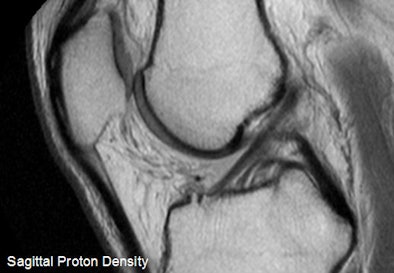

| Above, sagittal proton density-weighted image through the lateral meniscus from a 52-year-old male with interior knee pain. There is a short radial tear, which was seen only on the sagittal MR image and was present on the arthroscopy, making the image a true positive. Below, midsagittal proton density-weighted image is of the ACL of a 49-year-old male. The ACL appeared morphologically normal on MRI, but demonstrated laxity in arthroscopy. An orthopedic surgeon ruled a partial tear, making the image a false negative. Images courtesy of Asheesh Harsha and New York University. |